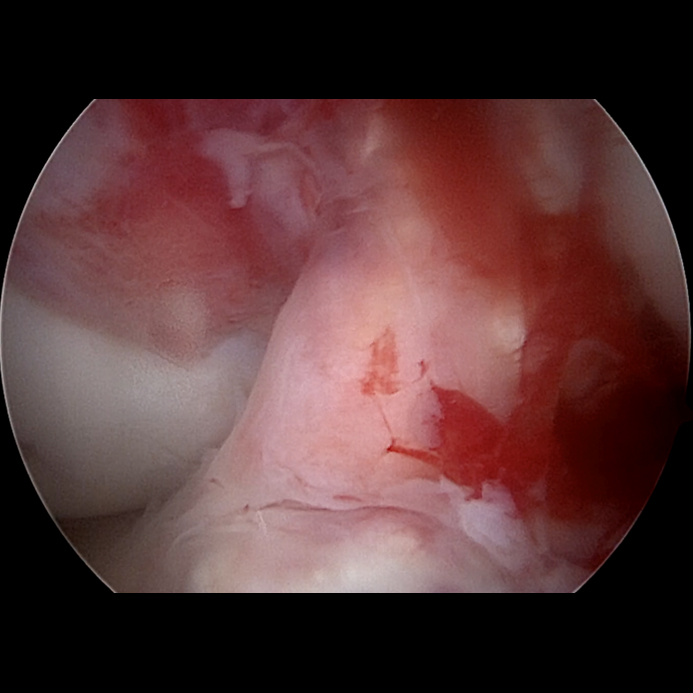

Der pathophysiologische Mechanismus einer vorderen Kreuzbandruptur schließt eine isolierte Bandverletzung aus und führt in der Regel zu Begleitverletzungen unterschiedlicher Schweregrade [5 – 7]:

- Posterolaterale Tibiakopfimpression („Apple Bite Fracture“) mit anterolateraler Femurcondylenimpression

- Anterolaterale Kapsel-Bandverletzungen & Einblutungen (Partialläsionen) Popliteusehne

- Dorsale Kapselverletzung

- Posteromediale Meniskus-Kapsel-Bandverletzungen (u. a. „Ramp-Lesion“)